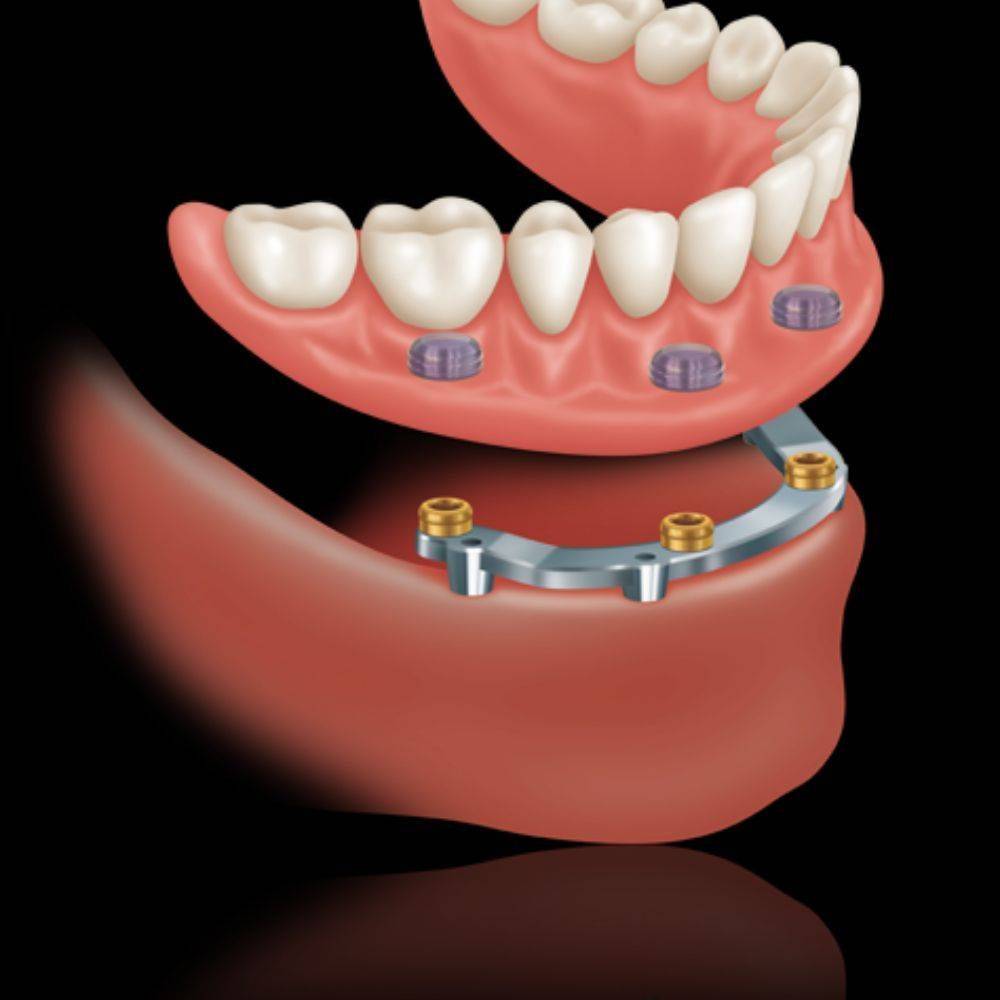

Ha a páciens már régen elvesztette a fogait az az eset állhat elő, hogy a csontfelszívódás miatt már nem lehet fix megoldást készíteni, mert az állkapocs elülső részén is felszívódott a csont. Ebben az esetben 2-3-4 implantátum beültetése után ezekre az implantátumokra egy speciálisan készített fogsort, az úgynevezett overdenture-t lehet rögzíteni.

Ennél a megoldásnál egy fix csavarozott stég kerül az implantátumokra, erre rögzül a fogsor, mely jellegében a hagyományos műfogsorra hasonlít, de az implantátum miatt annál sokkal stabilabb, és egyáltalán nem mozog. Ezenkívül az implantátumok itt is stimulálják a csontot, tehát megáll a csont sorvadása.